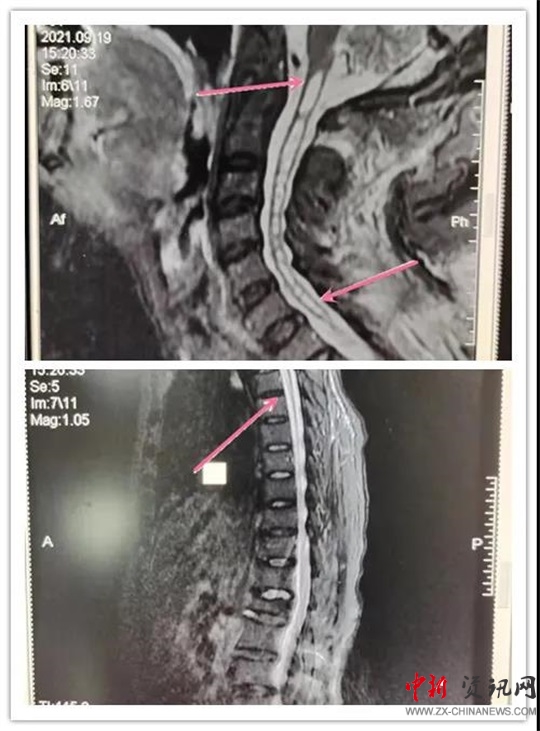

患者,女,70歲,六年前患脊髓空洞癥在某醫(yī)院行“脊髓空洞蛛網(wǎng)膜下腔分流手術(shù)”后病情好轉(zhuǎn)。近段時間,因“后肩部疼痛,無痛溫覺喪失,雙下肢疼痛、無力逐漸加重”癥狀加重,來汝南縣人民醫(yī)院就診,行MR檢查診斷為“頸胸脊髓空洞”。神經(jīng)外科副主任沈明輝認真研究了患者的病情和 MR片子,認為手術(shù)可行,隨即收住患者到科室;颊呷朐汉,完善了術(shù)前檢查,由于患者年事已高,患有高血壓、心臟病等疾病,使病情更加復(fù)雜,手術(shù)難度風險進一步加大。手術(shù)團隊組織了全科會診,對患者手術(shù)情怳進行了分析。如果不做手術(shù),病情進一步發(fā)展,患者雙下肢會截癱,再做手術(shù)也很難恢復(fù)。在得到患者家屬的理解和支持后,根據(jù)患者的病情,手術(shù)團隊反復(fù)討論術(shù)中可能出現(xiàn)的問題:完善圍手術(shù)期應(yīng)急預(yù)案,制定精準的治療及手術(shù)方案,擇期為患者成功實施了“頸胸脊髓空洞胸腔引流”手術(shù)。術(shù)后患者雙下肢肌力明顯好轉(zhuǎn),正在康復(fù)中。

手術(shù)后